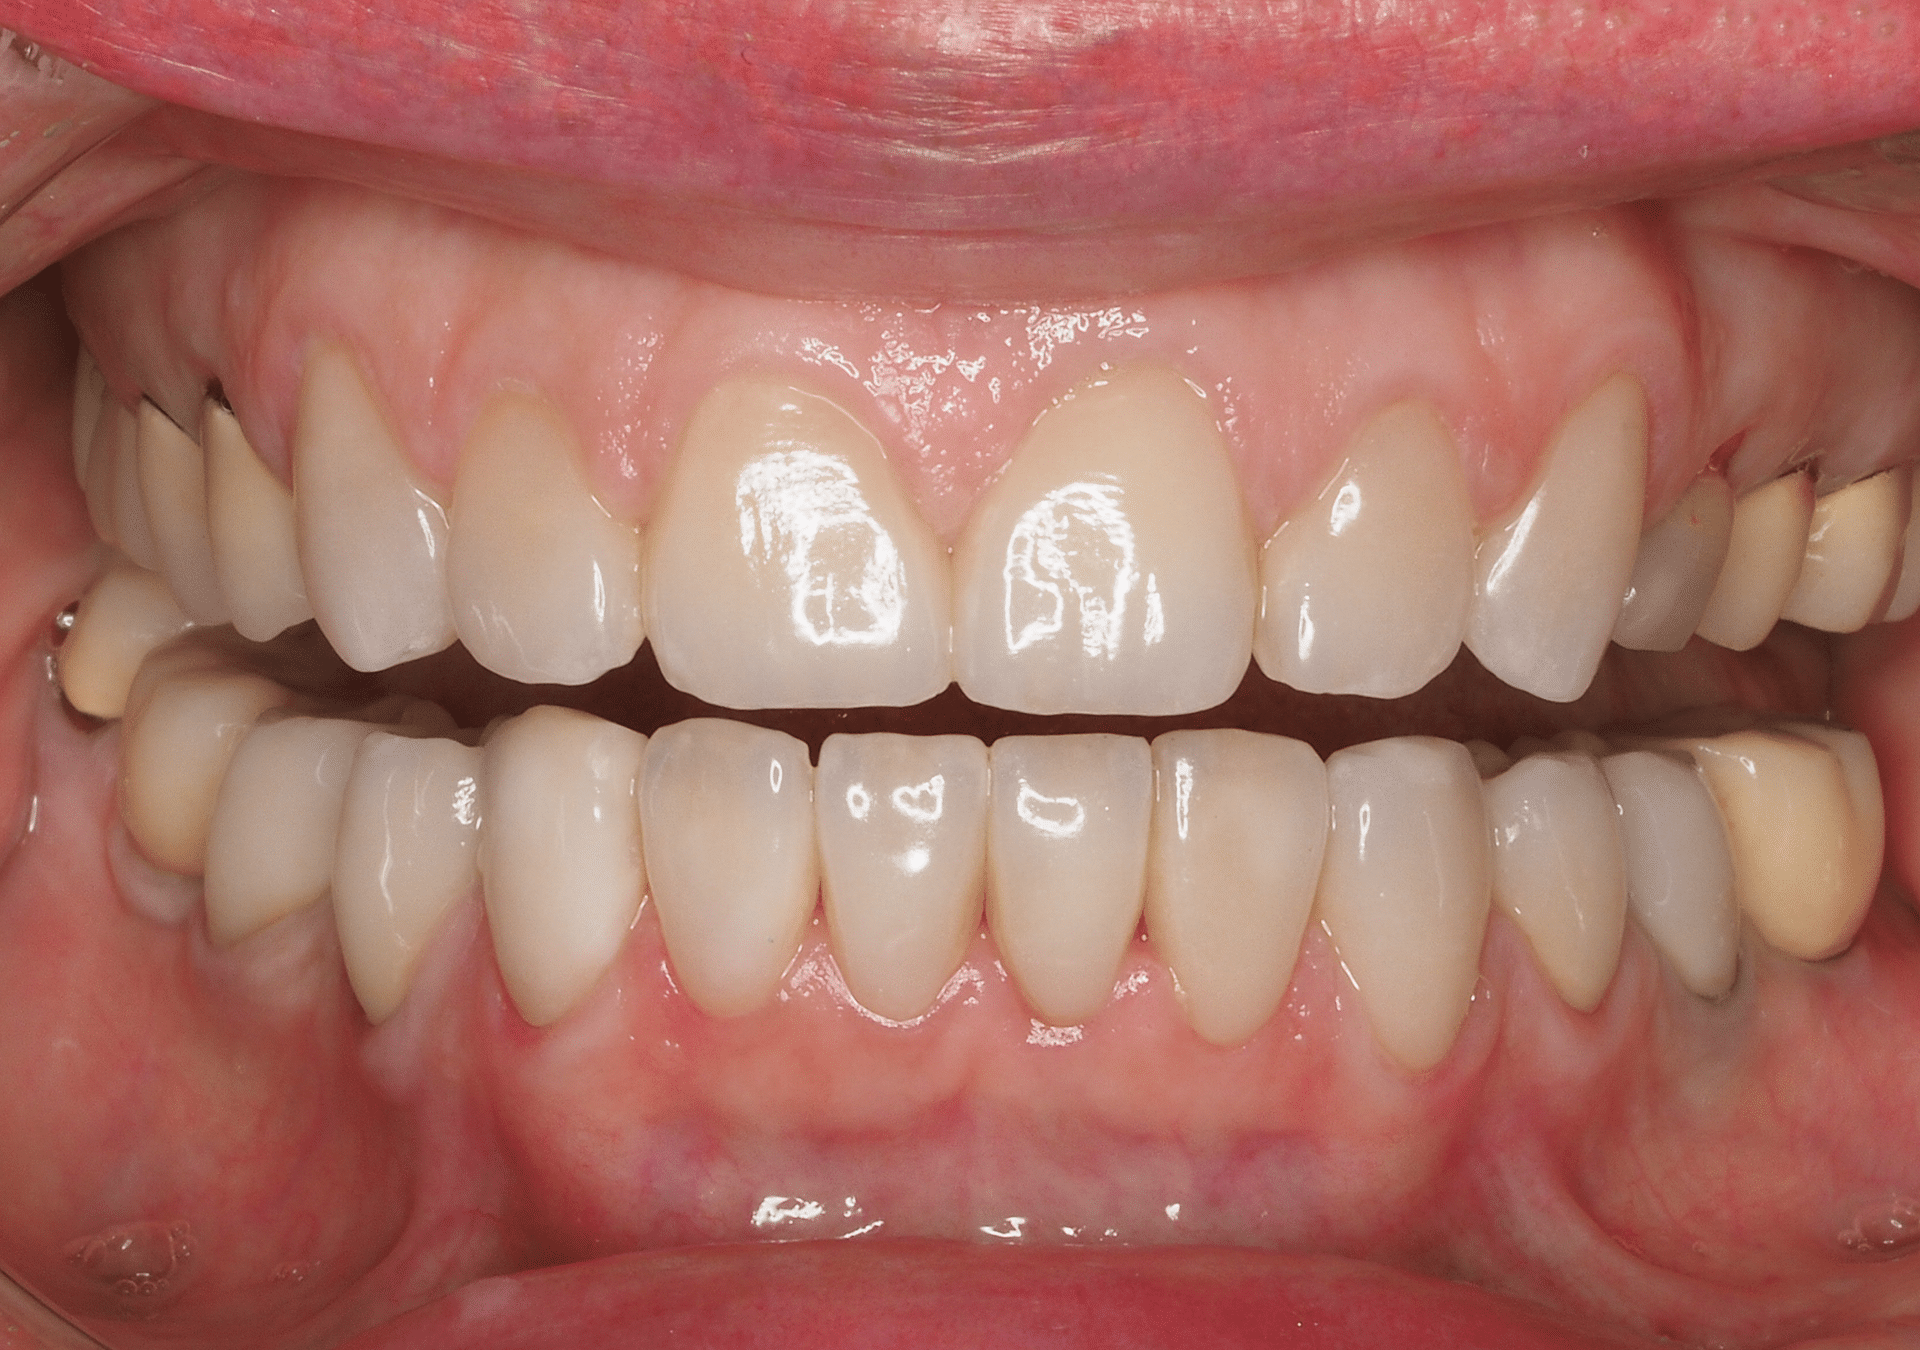

Restauración cerámica

- Experiencia en la rehabilitación de casos complejos.

- Diseño de sonrisa y prueba estética previos para visualizar los resultados antes de iniciar el tratamiento.

- Coordinación con laboratorios de máximo nivel para lograr resultados estéticos y funcionales excelentes.

Restauración

con composite (Resinas)

- 25 años de experiencia en restauraciones de resina de composite tanto en sectores anteriores como posteriores.

- Resultados estéticos comparables a la cerámica, de larga durabilidad.